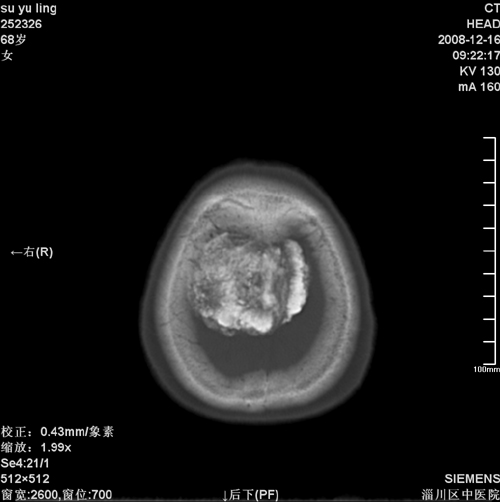

女,68岁,左侧肢体活动不利。

病灶比较均匀钙化,水肿明显,紧贴颅顶与大脑镰并跨越大脑镰----支持脑膜瘤

脑袋里长核,少见。支持脑膜瘤钙化考虑。

头一次看到这么大钙化脑膜瘤,且其周水肿范围太大